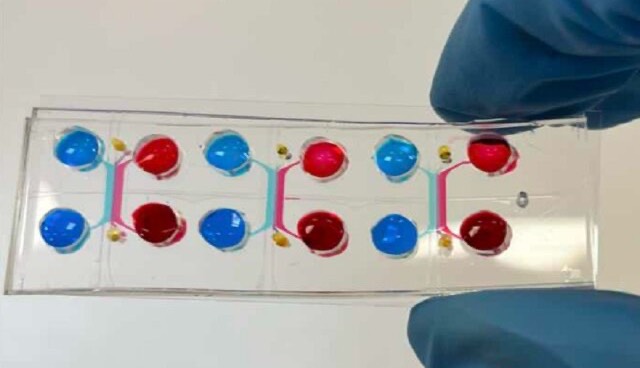

تولید میکروحبابهای لیپیدی برای ارتقای دقت تصویربرداری سونوگرافی